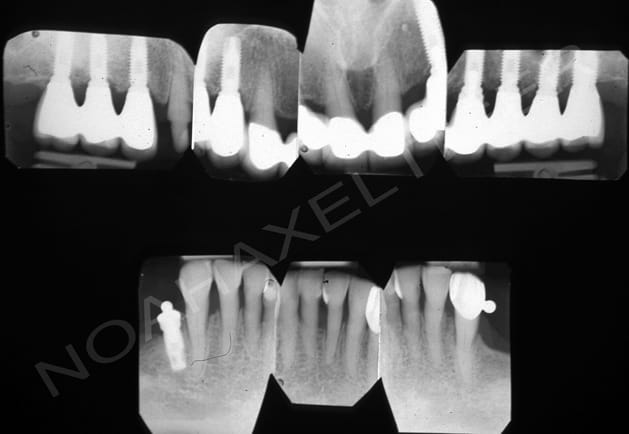

J'ai traité il ya de cela quelque temps un cas de réhabilitation globale sur terrain paro. Comme toi ikimine j'ai du faire face à un effondrement de DV, ce qui m'a amené à combiner paro, implanto, prothétique conventionnelle et occluso.

Voila les photos et radios initiales :

Radio initiales dq0rlp - Eugenol